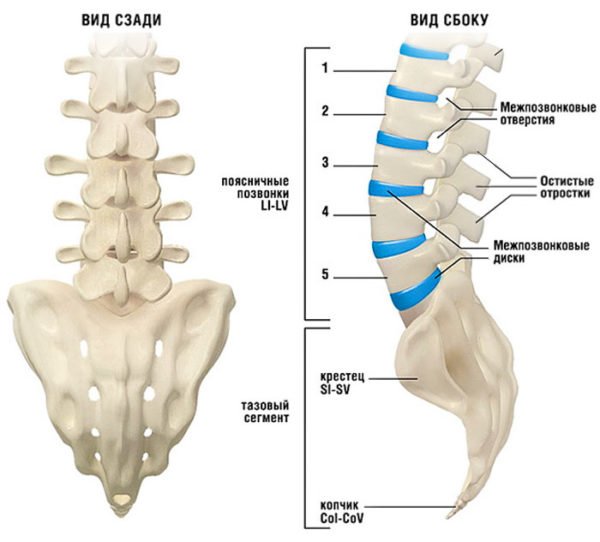

Поясничная | В этой зоне позвоночных сегментов всего пять. Они представлены обозначениями L1 — L5 и являются самыми крупными. В этой части дуги существует плавный изгиб, который является соединительным «мостиком» грудной и крестцовой зоны. На долю поясничных позвонков приходится самая тяжелая работа. Они несут самую большую нагрузку, амортизируют все тело, выдерживают давление его верхней части и отвечают за любое движение (пространственное перемещение) – от ходьбы до прыжков и бега. Патологии, деформации, травмы чаще всего происходят именно в поясничной зоне. |

Поясни́чные позвонки́ (лат. vertebrae lumbales) — пять нижних позвонков у человека с 20-го по 24-й, считая сверху. Поясничный отдел позвоночника соединяется ниже с крестцом (нижний поясничный позвонок L5 соединяется с верхним крестцовым позвонком S1), выше — с грудным отделом позвоночника (L1 соединяется с нижним грудным позвонком Th12).

Тело поясничного позвонка больше в ширину, чем спереди назад. Ширина больше высоты.

От тела позвонка назад идёт дуга, замыкающая позвоночное отверстие и переходящая далее в остистый отросток. На плоскости дуги в обе стороны расположены поперечные отростки, которые являются рудиментами рёбер. У основания поперечных отростков поясничных позвонков заметен рудимент истинных поперечных отростков (processus accessorius), который при большой длине (4 мм) приобретает форму шила (processus styloideus). Авторы М. Г. Привес, Н. К. Лысенков, В. И. Бушкович замечают, что его не следует принимать за патологическое образование. На верхней и нижней гранях дуги расположены парные верхние и нижние суставные отростки. В четырёх верхних поясничных позвонках остистые отростки направлены прямо назад, суставные расположены сагиттально. Позвоночные отверстия, начиная со второго поясничного позвонка, постепенно сужаются, что связано с анатомией спинного мозга.

Тело пятого поясничного позвонка в направлении к остистому отростку имеет клиновидную форму, при этом оно наклонено вперед, так как крестцовая кость направлена назад, формируя кифоз. Суставные отростки размещены в полуфронтальной, полусагиттальной плоскостях.

Поясничные позвонки образуют поясничный лордоз. Поясничный лордоз формируется во время освоения ребёнком положения стоя и ходьбы. На поясничный отдел позвоночника выпадает самая выраженная амортизирующая функция. К старости эта функция ослабляется.

Поясничные позвонки наиболее массивные и крупные во всём позвоночнике, с увеличением от первого поясничного к пятому, что объясняется максимальной нагрузкой на нижний отдел позвоночника. Позвонки грудного отдела и крестец малоподвижны, что требует от позвонков поясничного отдела повышенной подвижности. Пять поясничных позвонков человека и крестец образуют пять позвоночно-двигательных сегментов, что обеспечивает принципиальную возможность поворотов корпуса в стороны, движений корпуса в сагиттальной и фронтальной плоскости, а также комбинированные повороты и наклоны. Наличие сильных мышц поясницы помогает осуществлять движения даже с дополнительной нагрузкой.